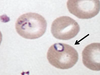

Plasmodium vivax (ring, trophozoite)

Plasmodium vivax (ring, trophozoite – note Schuffner’s dots)

Plasmodium vivax (ring)